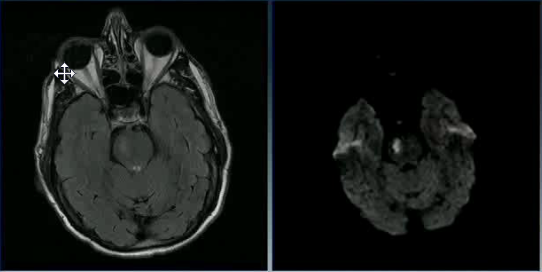

A 45 y/o woman with hypertension is resuscitated after a cardiac arrest. On day three she is able to move her face, hands, and feet, but is unable to move her limbs. A T2W1 MRI is taken at this time and is attached.

What is the general pathogenesis behind her symptoms and the MRI findings?

Hypotension secondary to cardiac arrest caused ischemia within the cerebrum, which has damaged her primary motor cortex bilaterally.

What cellular change is causing the bright vertical bands in each hemisphere?

Cytotoxic edema secondary to ischemia. The ischemia disrupts metabolism, which shuts down the Na+/K+/ATPase and causes cellular retention of Na+ and water.

Recall that on a T2W1 MRI, fluid (including water and CSF) is bright (as well as fat).

Why is the cellular change visaulized by the MRI localized to vertical bands?

This injury is a watershed infarction between the areas perfused by the ACA and MCA. The MCA area of the brain is especially susceptible to ischemia, and so its watershed area with the ACA will be the first to suffer. The bright vertical bands show cellular injury in the watershed zones across the entire cerebrum.